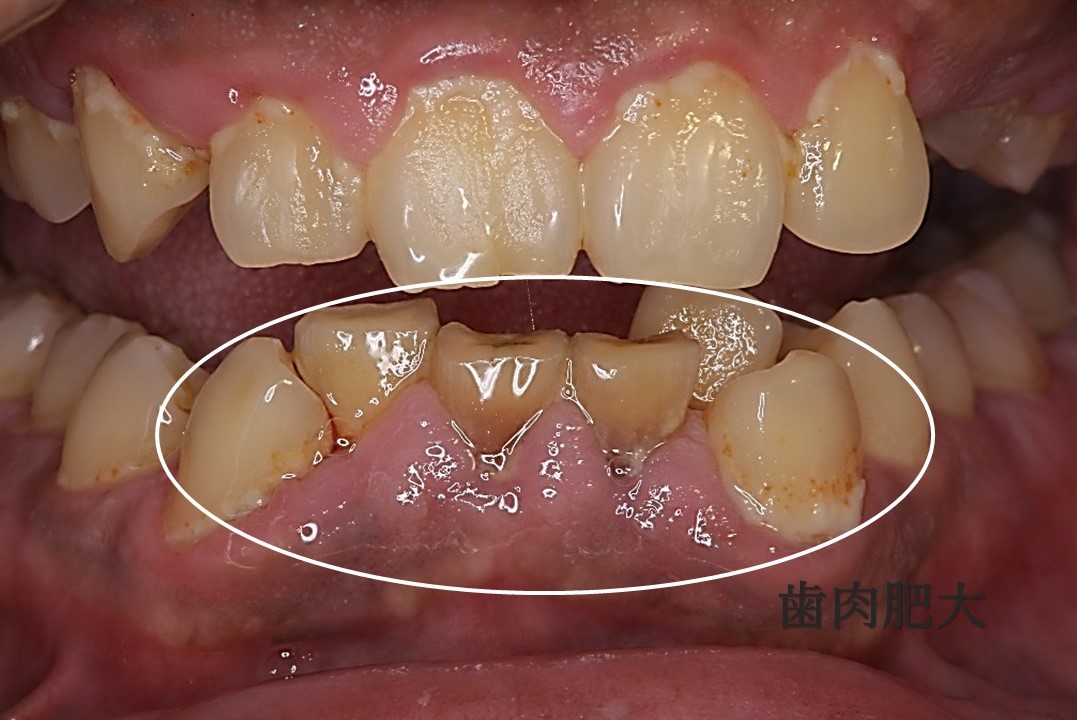

歯肉輪郭形成のプロセスには、歯の周囲の余分な歯肉組織を切除または除去することが含まれます。歯肉退縮がある場合、この処置には歯肉組織の修復が含まれます。

しかし、歯科医が口腔の健康上の理由から歯肉の輪郭を整えることを推奨する場合もあります。

歯周病がある場合は、歯肉の輪郭形成が治療の選択肢になることがあります。しかし、歯科医はまず非外科的オプションで歯周病を治療しようとします。これには、細菌や感染症を殺すための抗生物質や、歯ぐきの健康を回復するための歯科クリーニングなどが含まれる場合があります。